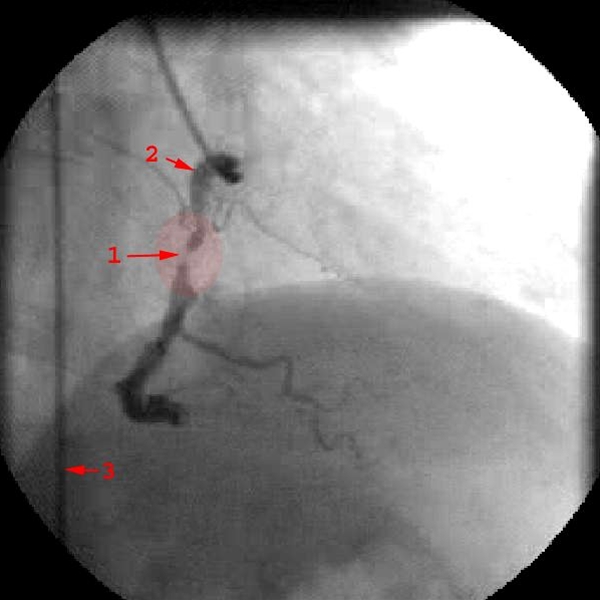

Forsnævring (markeret område) i højre koronararterie

1. Forsnævring (stenose)

2. Højre koronararterie (kranspulsåre)

3. Kateter i den store legemespulsåre (aorta)